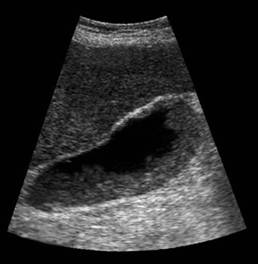

Pe langa alte semne, scaderea volumului colecistului constituie un criteriu de diagnostic al colecistitei cronice scleroatrofice litiazice.

Un volum vezicular redus mai poate fi intalnit in adenomiomatoza colecistului si in tumorile veziculare care ii ocupa treptat lumenul. De aceea, un colecist 'mic' si litiazic, la un pacient varstnic, trebuie investigat cu atentie, pentru a se evita omisiunea unui carcinom vezicular.

Colecistita cronica scleroatrofica litiazica